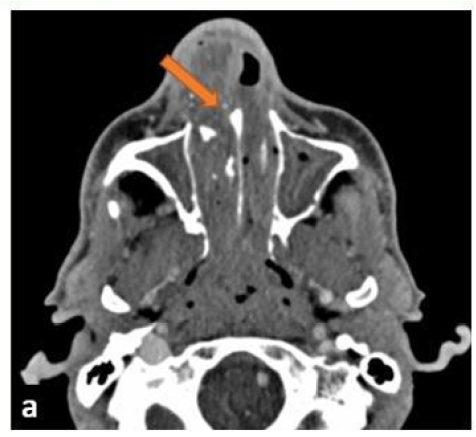

Inverted Papilloma: A Brain-Like Appearance in the Nose

N Amsiguine, S Habib Chorfa, F Touarsa, M Fikri, M Jiddane and N Kettani. 15(5): 115-118.